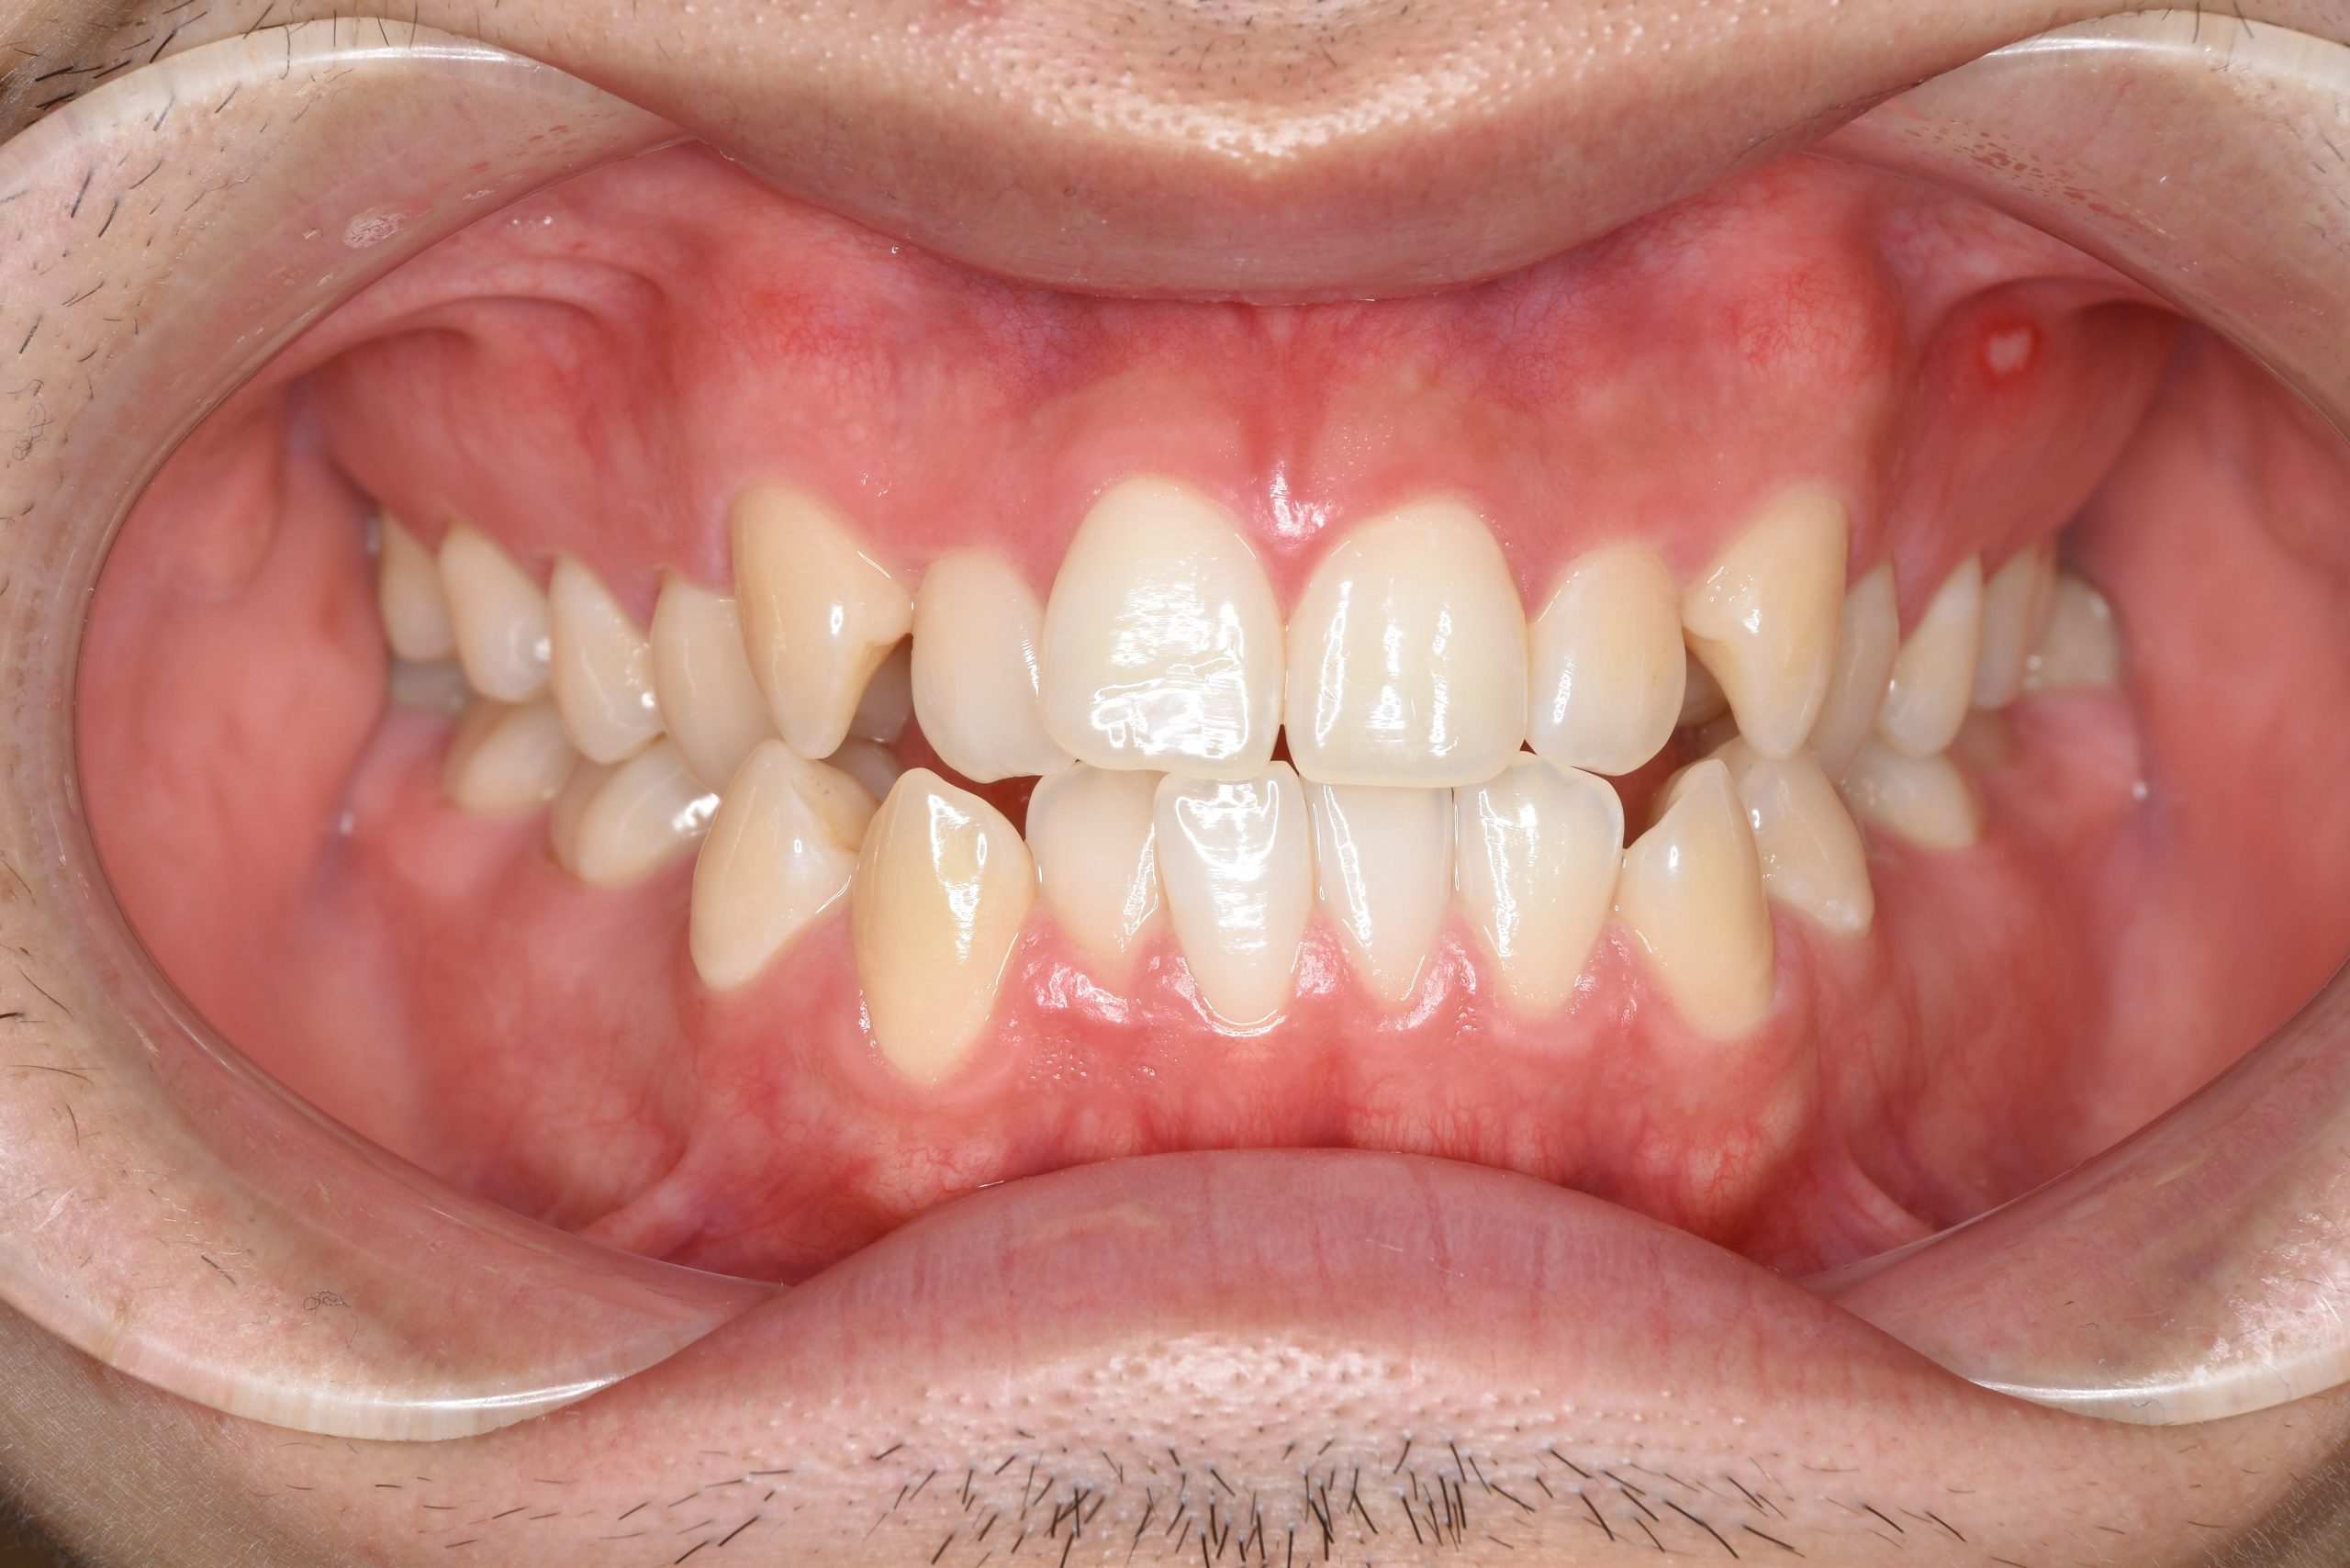

アフター

ワイヤー矯正治療|症例_495

主訴 受け口|かみ合わせ|面長

施術内容 MSEと下顎リンガルアーチを用いて上下顎骨を拡大した。

その後マルチブラケット装置とミニインプラントを用いて

非抜歯で歯牙を配列し、良好な咬合を獲得した。

下口唇の突出感と鼻閉症状は改善した。

治癒期間 2年1か月間